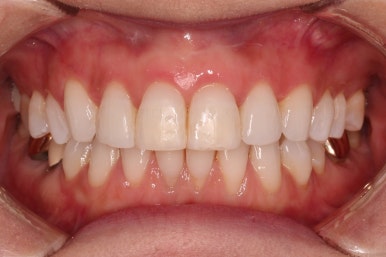

환자분이 원하시는 만큼 가지런해졌고, 부가적으로 생길 수 있는 부분들도 수용 가능한 선에서 잘 마무리가 되었습니다.

3개월이라는 빠른 기간 내에(심미보철 보다 약간만 더 긴 시간) 치아의 손상없이 마무리를 잘 했습니다.

물론 중간에 장치를 부착한 기간동안은 심미적으로 부담스러우셨겠지만요.

아래 앞니는 부분교정까지는 원하지 않으셔서 약간 다듬어 드리고 종료했습니다.

이상 부분교정과 앞니 심미보철을 고민하셨던 분을 연산동부분교정 잘 개선했던 치료사례였습니다.